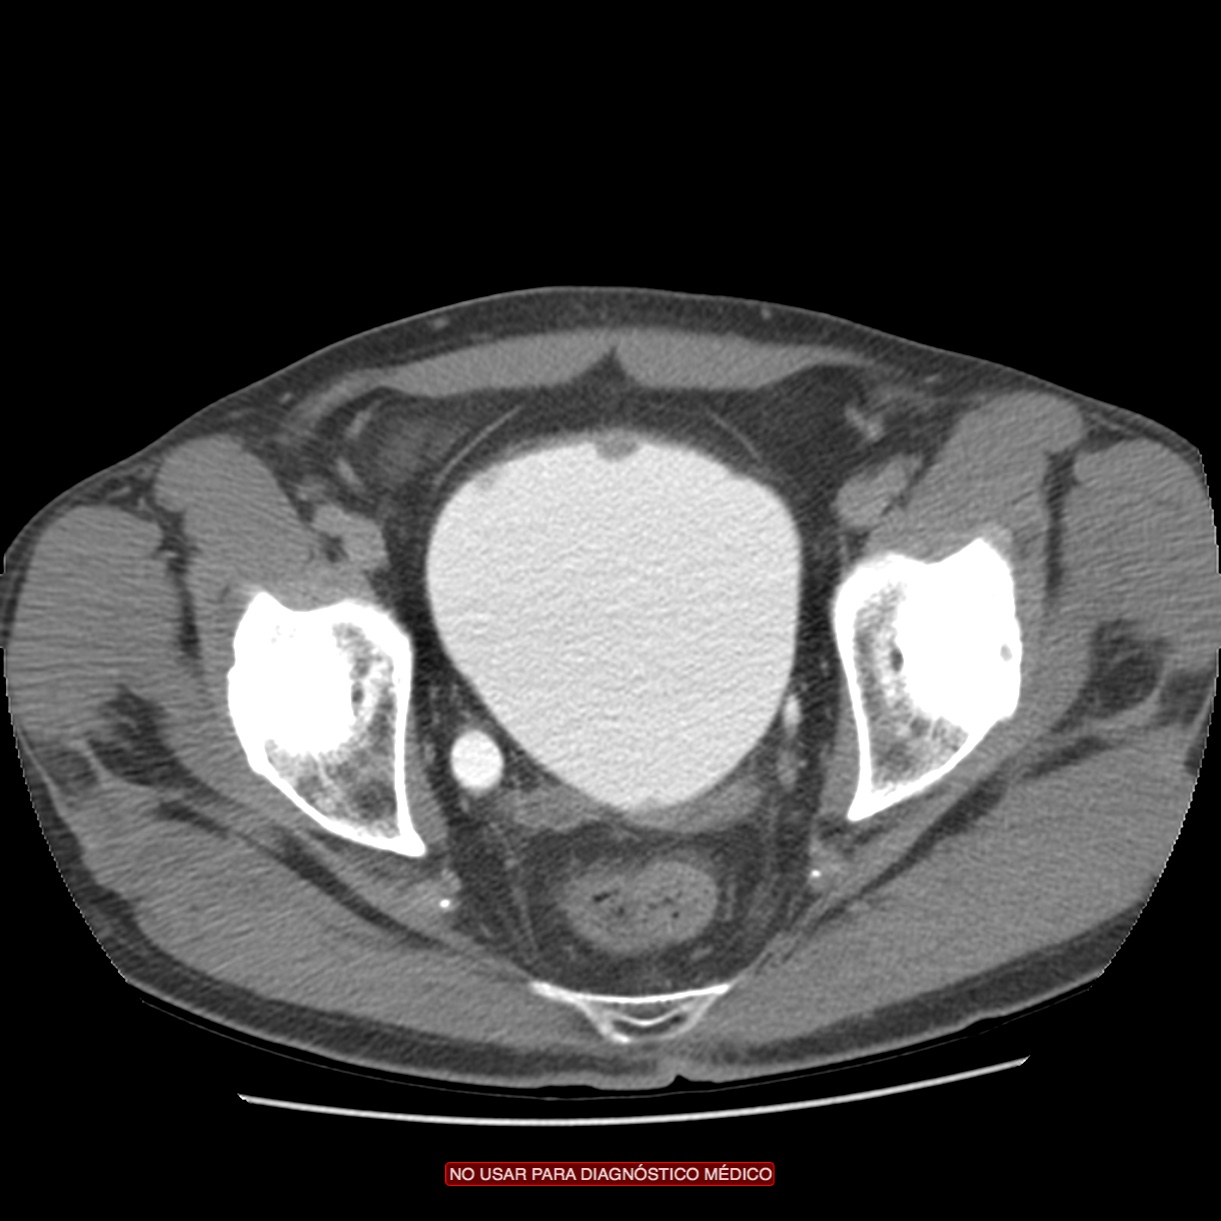

Paciente de 59 años con antecedentes personales de Cá de vejiga.

Se le realiza una Uro-Tc por seguimiento al año, aunque en esta ocasión el paciente refiere episodio de hematuria.

Tras el tratamiento de la recidiva y nefrostomía para la hidroureteronefrosis, vuelve acudir al hospital a los 9 meses por episodio de dolor en FD y malestar general. Se realiza una ecografía de urgencias.

Se realiza nueva TC bifásico abdominopélvio y Uro TC.

- Ha desarrollado un tumor metacrónico en pelvis renal derecha, también responsable de la hidroureteronefrosis.